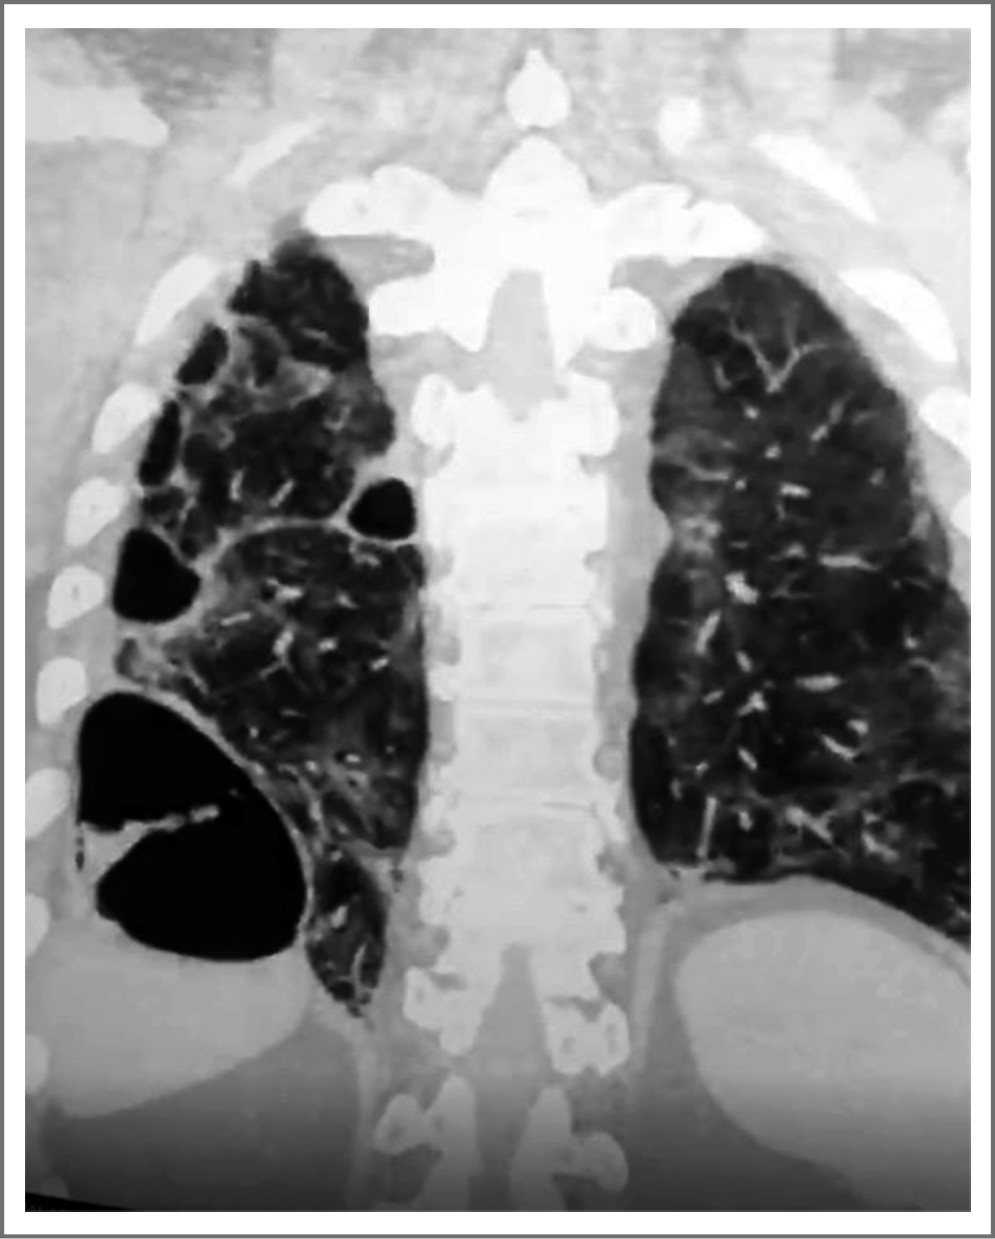

ФЛ развивается у больных COVID-19 на 3–4-й неделе от начала лихорадочного периода вирусного инфекционного заболевания. У отдельной группы больных фибротические изменения легочной паренхимы сочетаются с развитием буллезной болезни легких. На рис. 3 представлено персональное наблюдение за больным, перенесшим в тяжелой форме COVID-19; проводилась искусственная вентиляция легких в течение 10 дней. На КТ можно наблюдать множественные буллы, одна из них – гигантская. В просвете гигантской буллы виден обтурированный тромбом сосуд. Буллезные изменения развились на фоне выраженного ФЛ: объемное уменьшение легочной ткани, множественные тракционные бронхиолоэктазы; процесс ремоделирования легких, вызванный фиброзным процессом и образованием множественных булл.

Рис. 3. КТ органов грудной клетки больного, перенесшего в тяжелой форме COVID-19; буллезные изменения на фоне выраженного ФЛ. / Fig. 3. Thoracic CT of patients suffering from severe COVID-19; bulose changes against the background of pronounced pulmonary fibrosis.